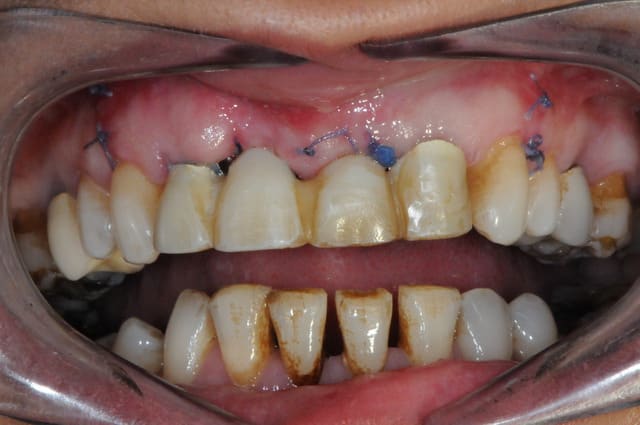

patiente 43 ans, très souriante, rigole tous le temps, fumeuse devant l'Eternel (1paquet/jour).

la parodontite et la mobilité sur 12 l'inquiète d'autan plus que les dents sont de plus en plus mobiles.

la 12 est perdue, mais également la 11 qui subit déjà une forte résorption gingivale.

21 et 22 pas beaucoup mieux.

on décide donc d'extraire 12-11-21-22, ROG, implantation et mise en charge immédiate. puis, chirurgie parodontal d'augmentation (surtout pour le secteur 11) et enfin bridge définitif avec chape en zircone. la patiente refuse catégoriquement une prothèse adjointe. elle est coquette

heureusement pour nous, car elle est toujours très souriante, elle ne découvre pas.